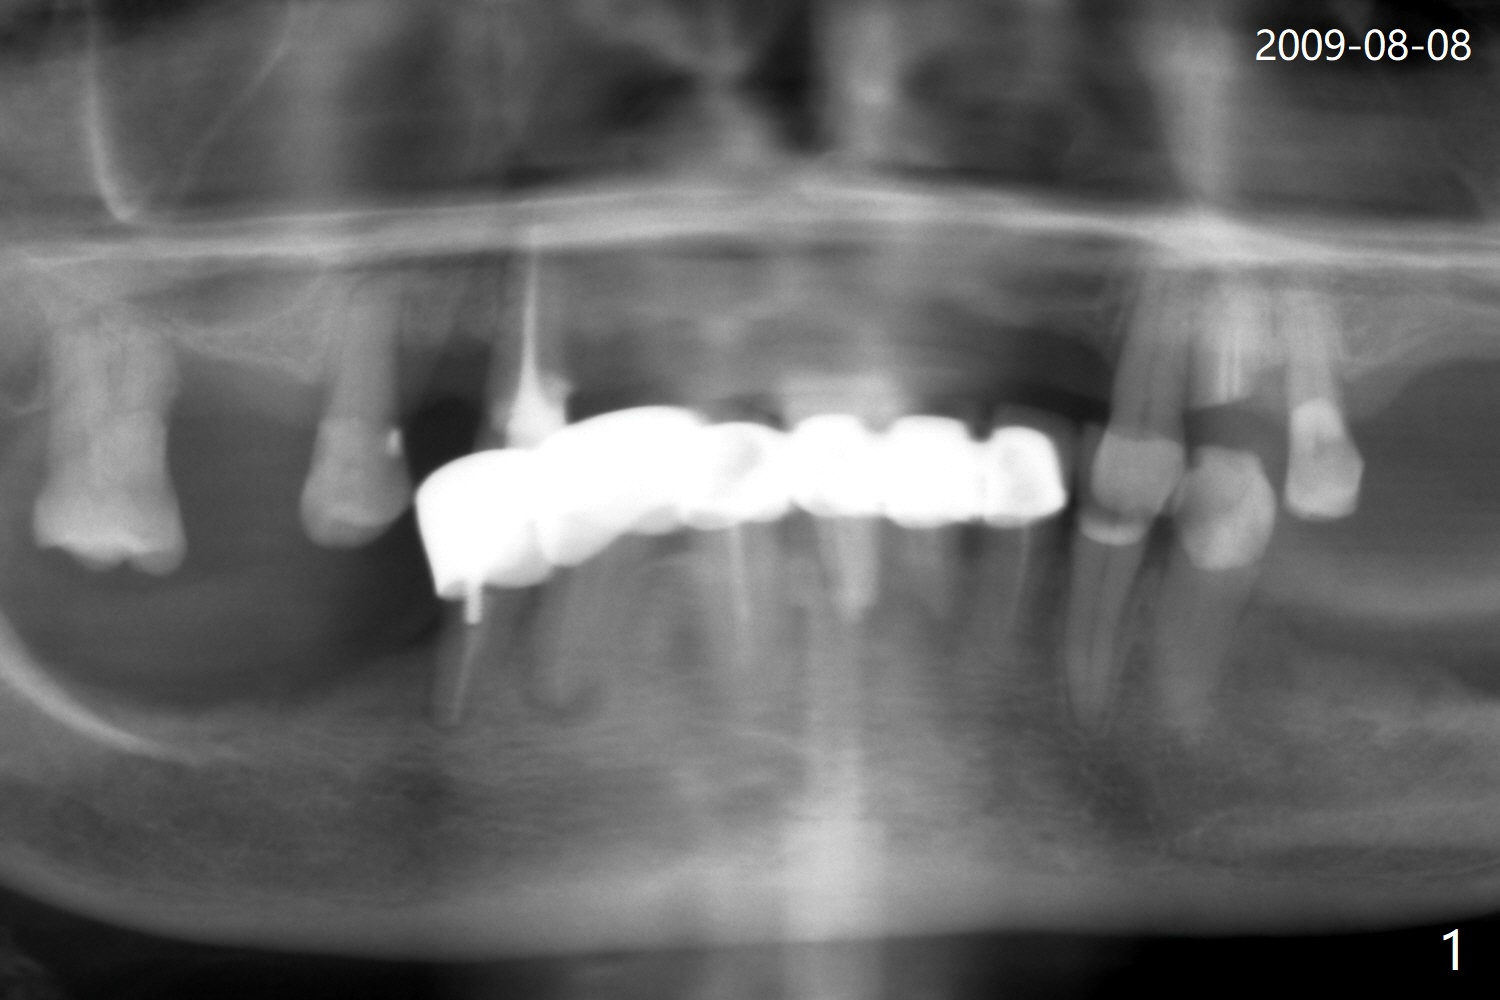

A 85-year-old woman has had poor dentition (Fig.1). She requests extraction of the tooth #21 with crown fracture (Fig.2 <) and PARL (*). Although the buccal plate is low, Vanilla/Osteogen mixture is used for socket preservation (Fig.3 *), while BioXclude is used to cover the socket opening. Three to four 5-0 PGA sutures appear to be able to close the socket. It is expected that the membrane with several growth factors facilitates wound healing. It seems that the bottom of the socket is not fully packed with the bone graft (Fig.3 ?). Bone condenser should have been utilized. The socket appears to heal (due to BioXclude?) with minor buccal plate collapse 1 week postop (Fig.4). Titanium membrane should have been used.